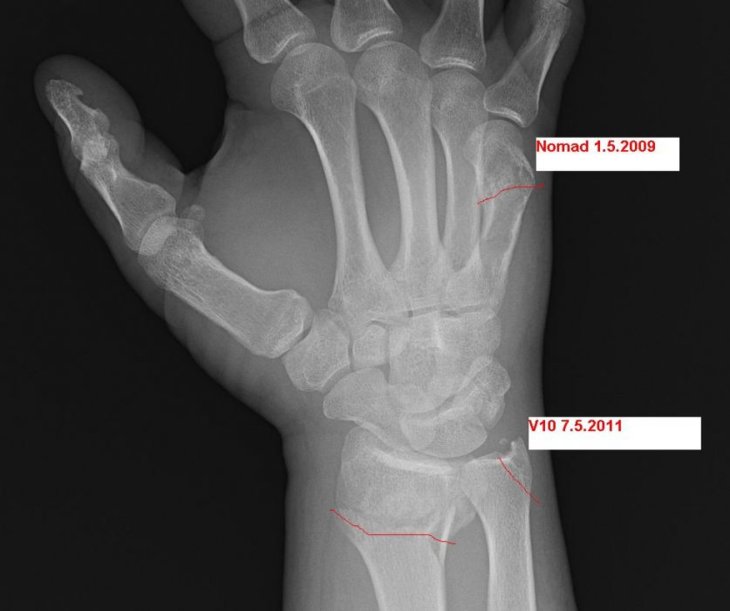

Heh úplně stejná zlomenina jako, akorát jsem měl kosti víc rozjetý od sebe. Zápěstí je hnus, tak ať ti dobře dopadne…

No to mě *****, ta nová fraktura je nemlich ta samá jako u mě.

Křivý? Určitě né. Říkali jak je to krásně rovný. Je vidět že zedničit by někteří lékaři nemohli :o)

Po tom Nomadovi to mas srostle spravne ? Prijde mi to nejake krive :D